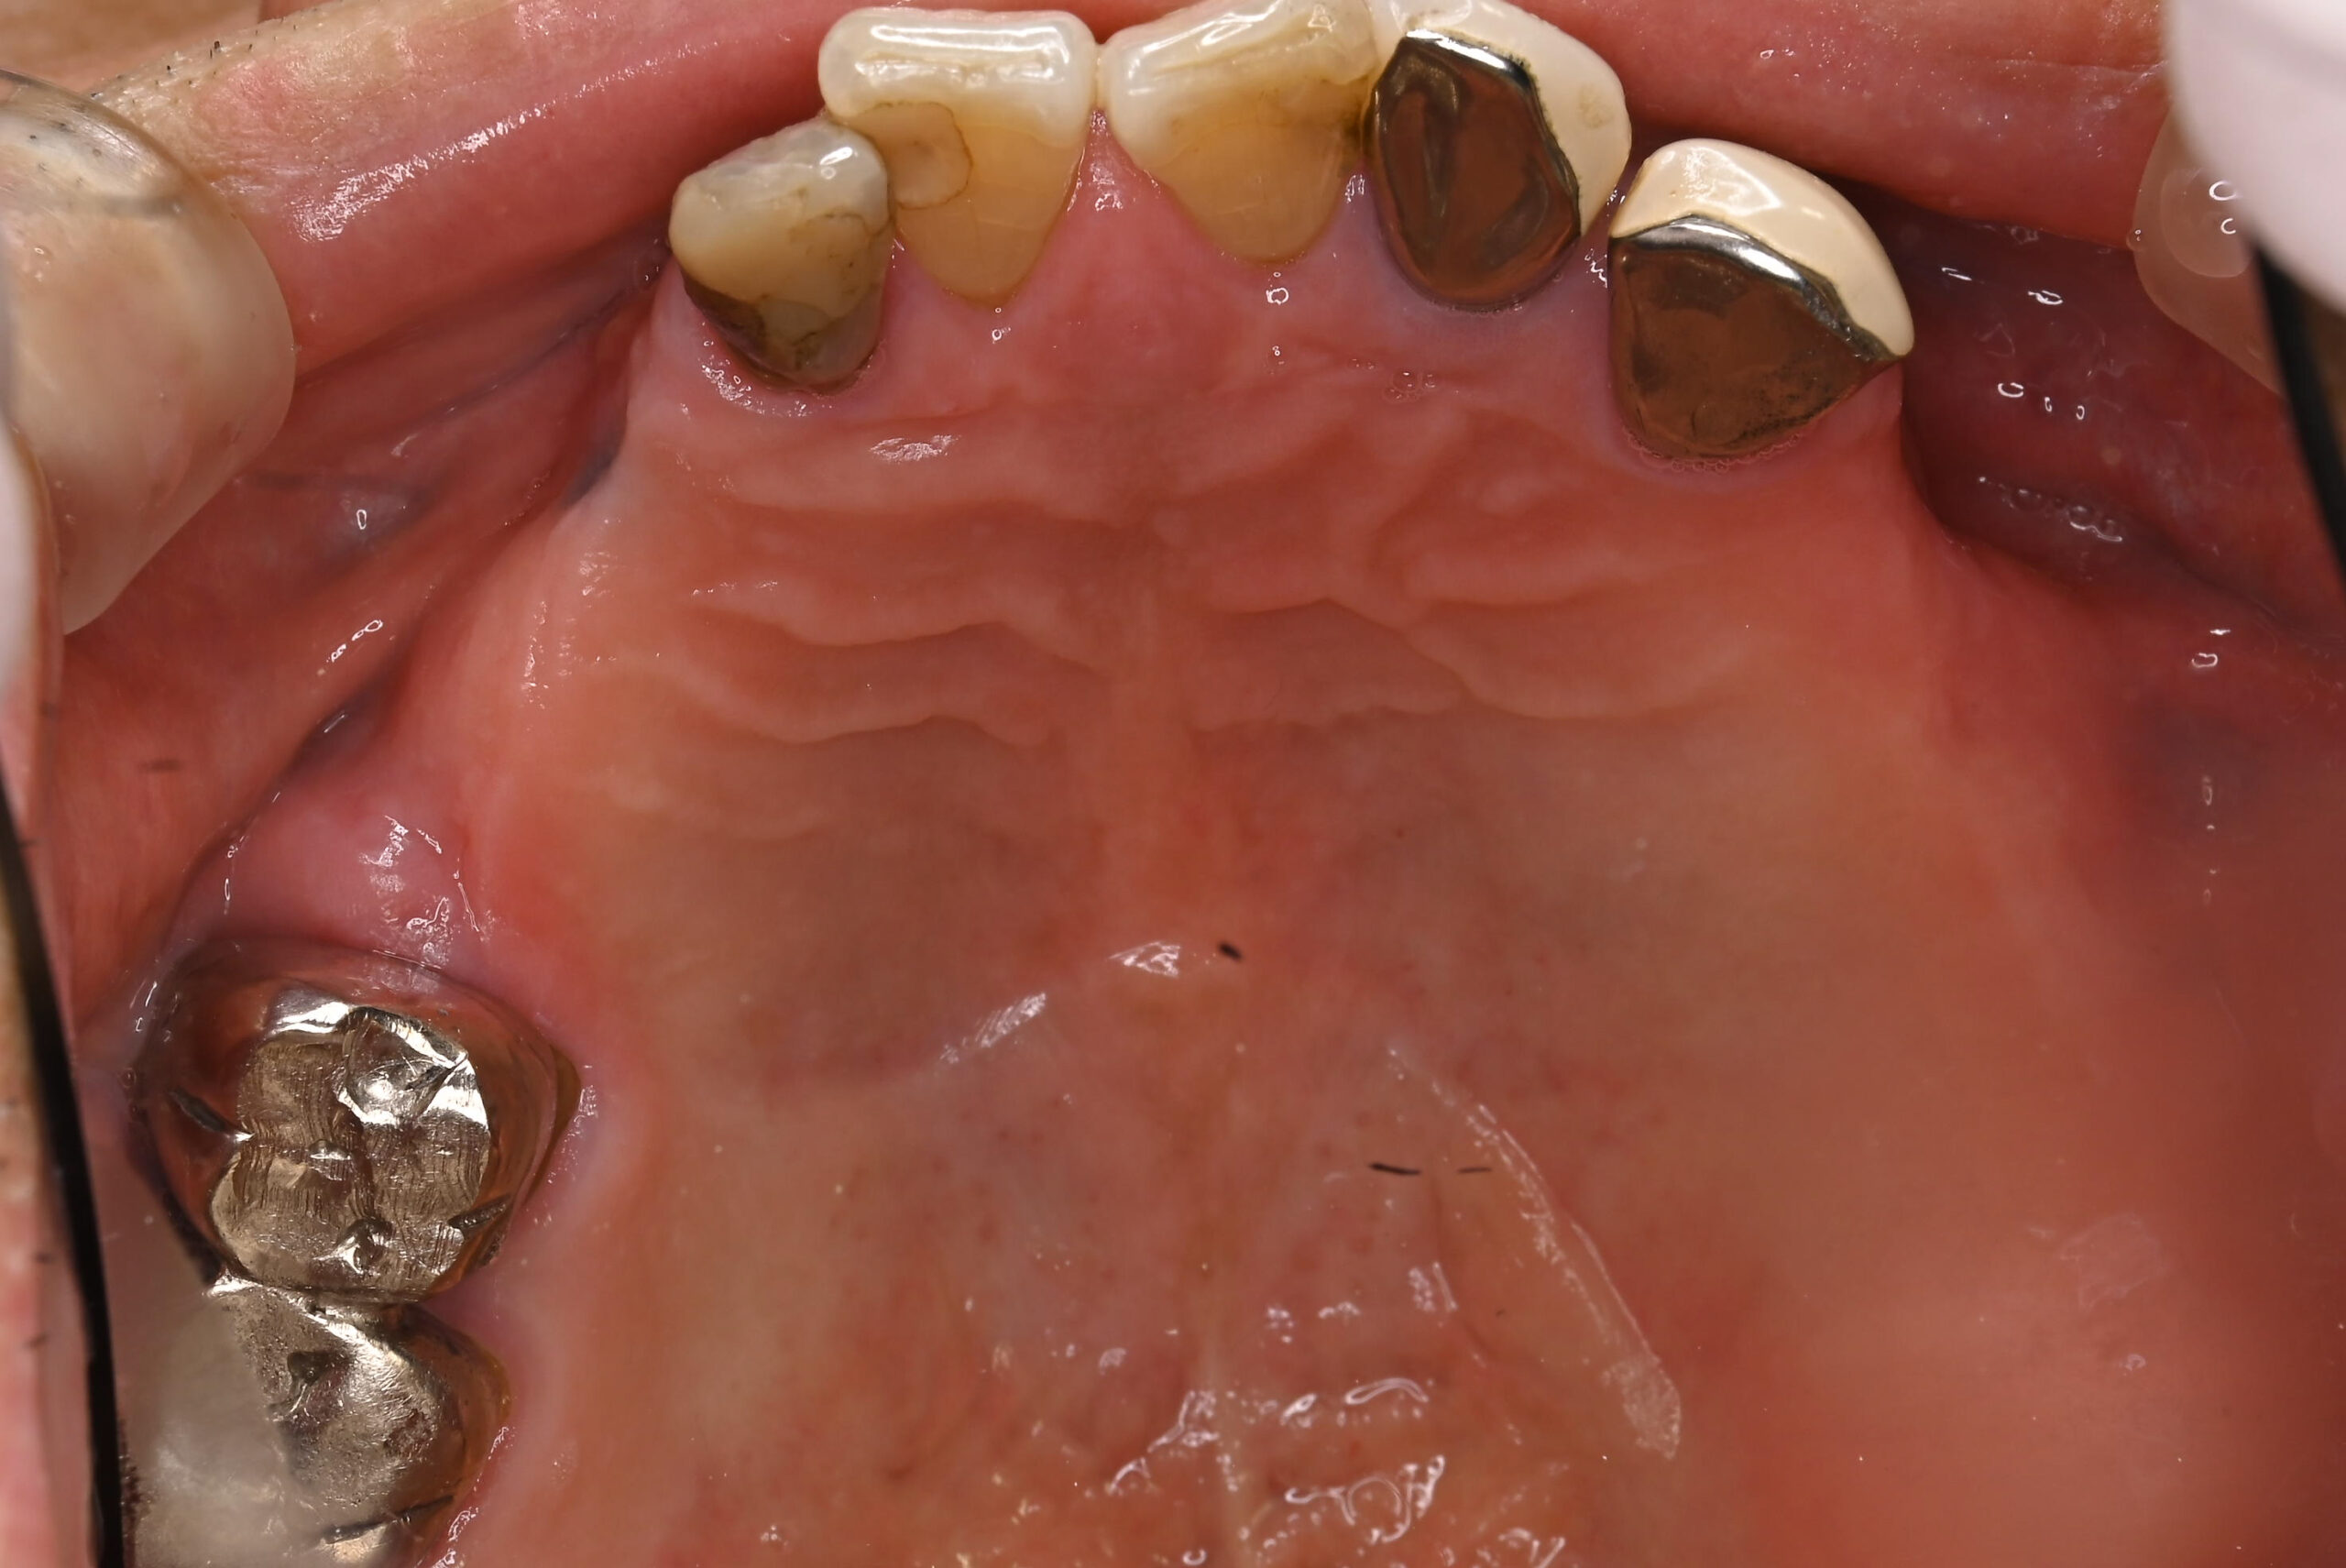

治療前写真2(口腔内写真)

-